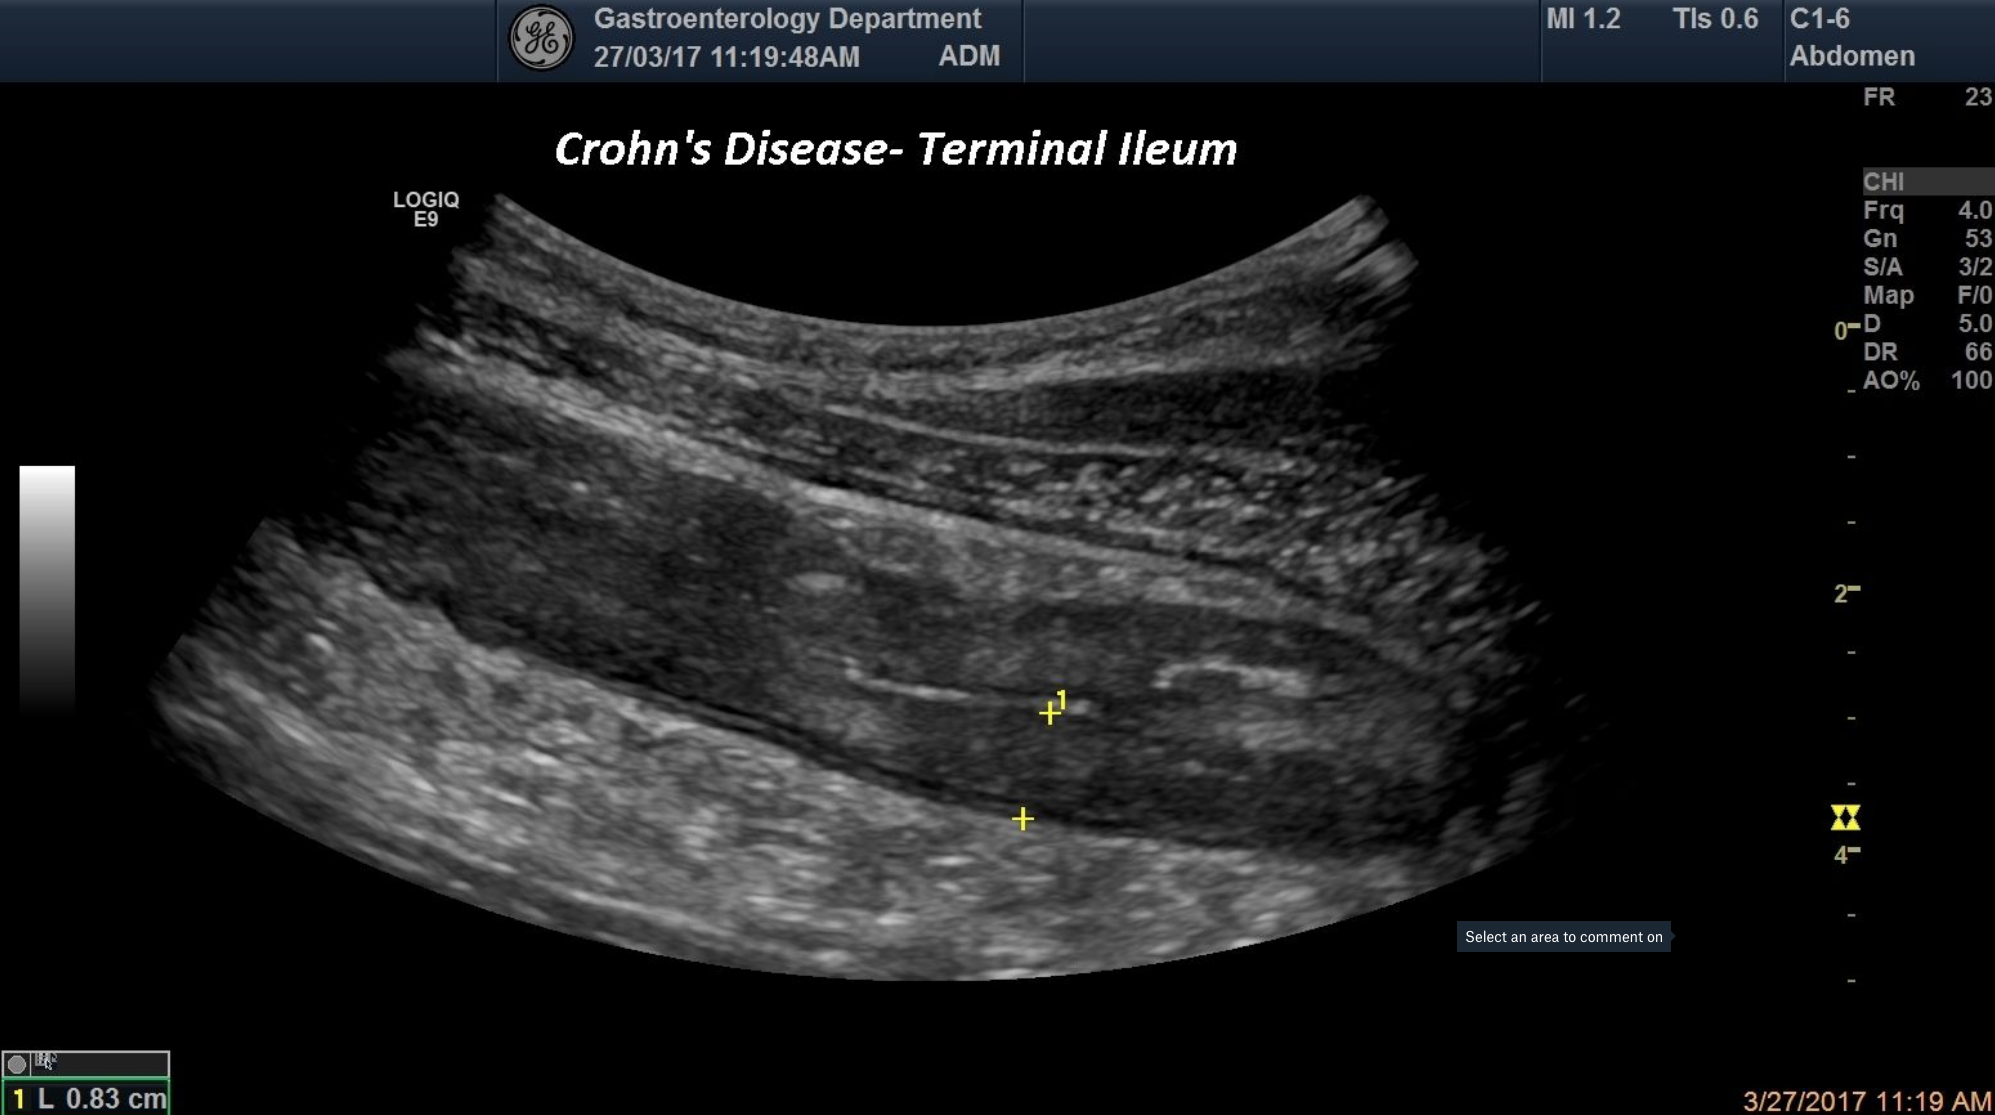

A 28 years old female was seen in the Gastroenterology ambulatory for IBS symptomatology. A wall thickening and the loss of the multi layer pattern of the terminal ileum was noticed in standard ultrasound

Crohn’s disease, terminal ileum, wall thickening